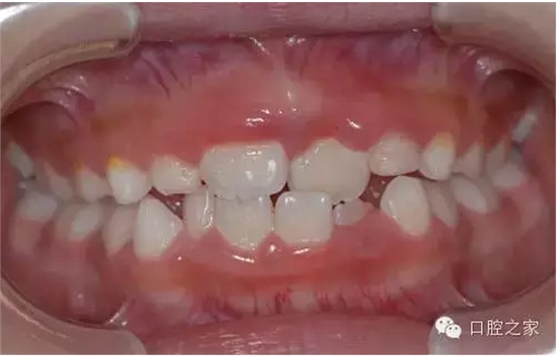

上下牙弓近遠中關系異??杀憩F為下頜前突,近中錯合及前牙反合。多由于不良哺乳姿勢,乳前牙滯留或早失,上恒切牙先天性缺失,不良習慣、乳尖牙磨耗不足,全身性疾病以及遺傳性下頜前突所致。因程度不同可表現為前牙反合,磨牙為中性合,嚴重病例則前牙反合、后牙近中合及下頜前突同時存在。

前牙反,顏面可表現為下頜前突,上頜發育不足的凹形側面形。